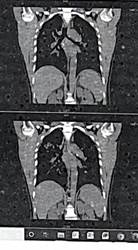

En la tabla 2 se pueden analizar los estudios paraclínicos realizados en agosto de 2023. En los estudios de imagen, la radiografía de tórax posteroanterior de agosto de 2023 (imagen 1) mostró opacidades bilaterales de predominio apical, tipo 2 de la Clasificación Internacional de la OIT. La tomografía computarizada (TC) toracoabdominal del mismo mes (imagen 2) evidenció opacidades bilaterales formando masas, principalmente en pulmón derecho, sin cavitaciones, desplazamiento bronquial por efecto de masa, nódulos subpleurales, alteración de arquitectura pulmonar; y una TC posterior realizada en clínica privada reportó imágenes hiperdensas en lóbulos superiores, probable cavitación ocupada en lóbulo superior derecho, fibrosis y patrón reticular grueso sin derrame pleural. Como parte del protocolo de estudio, se le realizaron las pruebas de función pulmonar donde se reportaron en febrero de 2024 una CVF (capacidad vital forzada) y VEF₁ (volumen de aire exhalado durante el primer segundo de la maniobra espiratoria forzada) al 60%, y en marzo de 2024 CVF 42% y VEF₁ 45%, confirmando deterioro funcional severo (imagen 3).

Imagen 2.

Tomografía computarizada de tórax.

Nota: Tomografía computarizada de tórax ventana pulmonar en corte coronal y axial, donde se evidenció opacidades bilaterales formando masas, principalmente en pulmón derecho.